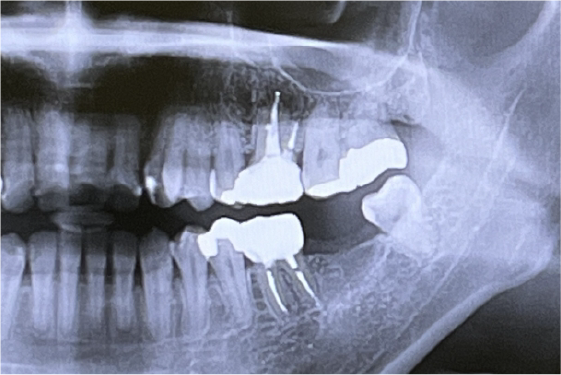

口腔内全体の状態を写すレントゲン、部位ごとの歯周組織や骨の状態まで診断可能なレントゲン検査により、虫歯や歯周病の進行具合、顎の関節の状態を診査します。